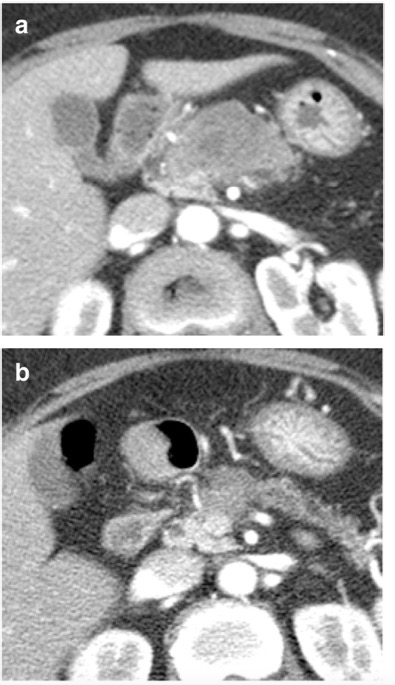

70歲女性,因胰腺癌接受新輔助治療。(a)在診斷時(shí)和(b)新輔助治療后的增強(qiáng)CT圖像。所有六位讀者對(duì)再分期CT的腫瘤可切除性評(píng)估為 "邊-可切除"。五位讀者評(píng)估腫瘤反應(yīng)等級(jí)為1(反應(yīng)良好)。由于腫瘤周圍的纖維化和粘連,進(jìn)行了門靜脈/腸系膜上靜脈切除和端對(duì)端吻合術(shù),但病理檢查沒有靜脈侵犯的證據(jù)。切緣為陰性,YpT2N0分期。